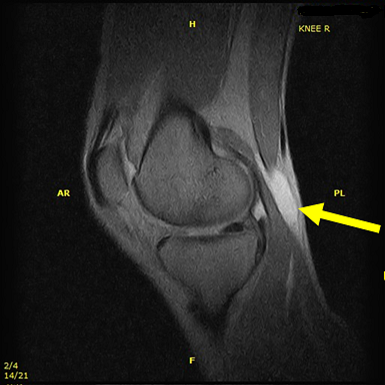

楽天市場】【内側半月板】《固定用》膝サポーター|エクスエイド。楽天市場】【内側半月板】《固定用》膝サポーター|エクスエイド。膝サポーター 膝 サポーター 医療用 医療 スポーツ 内側半月板。米10キロ 天のつぶ 雪若丸(各5キロ×1袋)。内側半月板損傷|おすすめの膝サポーター。半月板損傷 |SPORTS MEDICINE LIBRARY|ザムスト(ZAMST)。内側半月板損傷におすすめの膝サポーター集 コルセットミュージアム。半月板損傷 |SPORTS MEDICINE LIBRARY|ザムスト(ZAMST)。半月板損傷(断裂)meniscus-injury(rupture)について | ゆうき。右膝内側半月板損傷 前野整形外科 - 【公式】esaote 日本で唯一。外側半月板損傷|おすすめの膝サポーター。エクスエイドニー 固定用内側半月板損傷用 右膝用です。半月板損傷 – McDavid|サポータ-ブランドのマクダビッド。※外側半月板損傷 左膝膝としても使えます定価16980円でした。1度着用いたしました。円板状半月板損傷を治す!>膝サポーターのメソッド。固定力がとてもあり、安定してます。サイズM